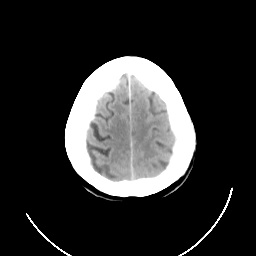

CT Study #3 -- Slice #24

[Home][Help][Clinical][Tour 1] Slice 24